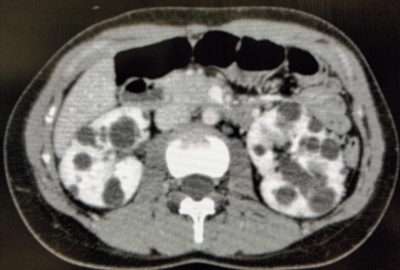

尿所見:蛋白(-)、糖(-)、潜血反応(-) 。腹部造影CTを別に示す。母と同病であると診断された。近く、結婚予定で挙児希望がある。パートナーの家系に同病の人はいない。